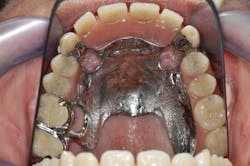

Figs. 3a, b, and c: Extraction of the upper incisors and maxillary removable acrylic placement